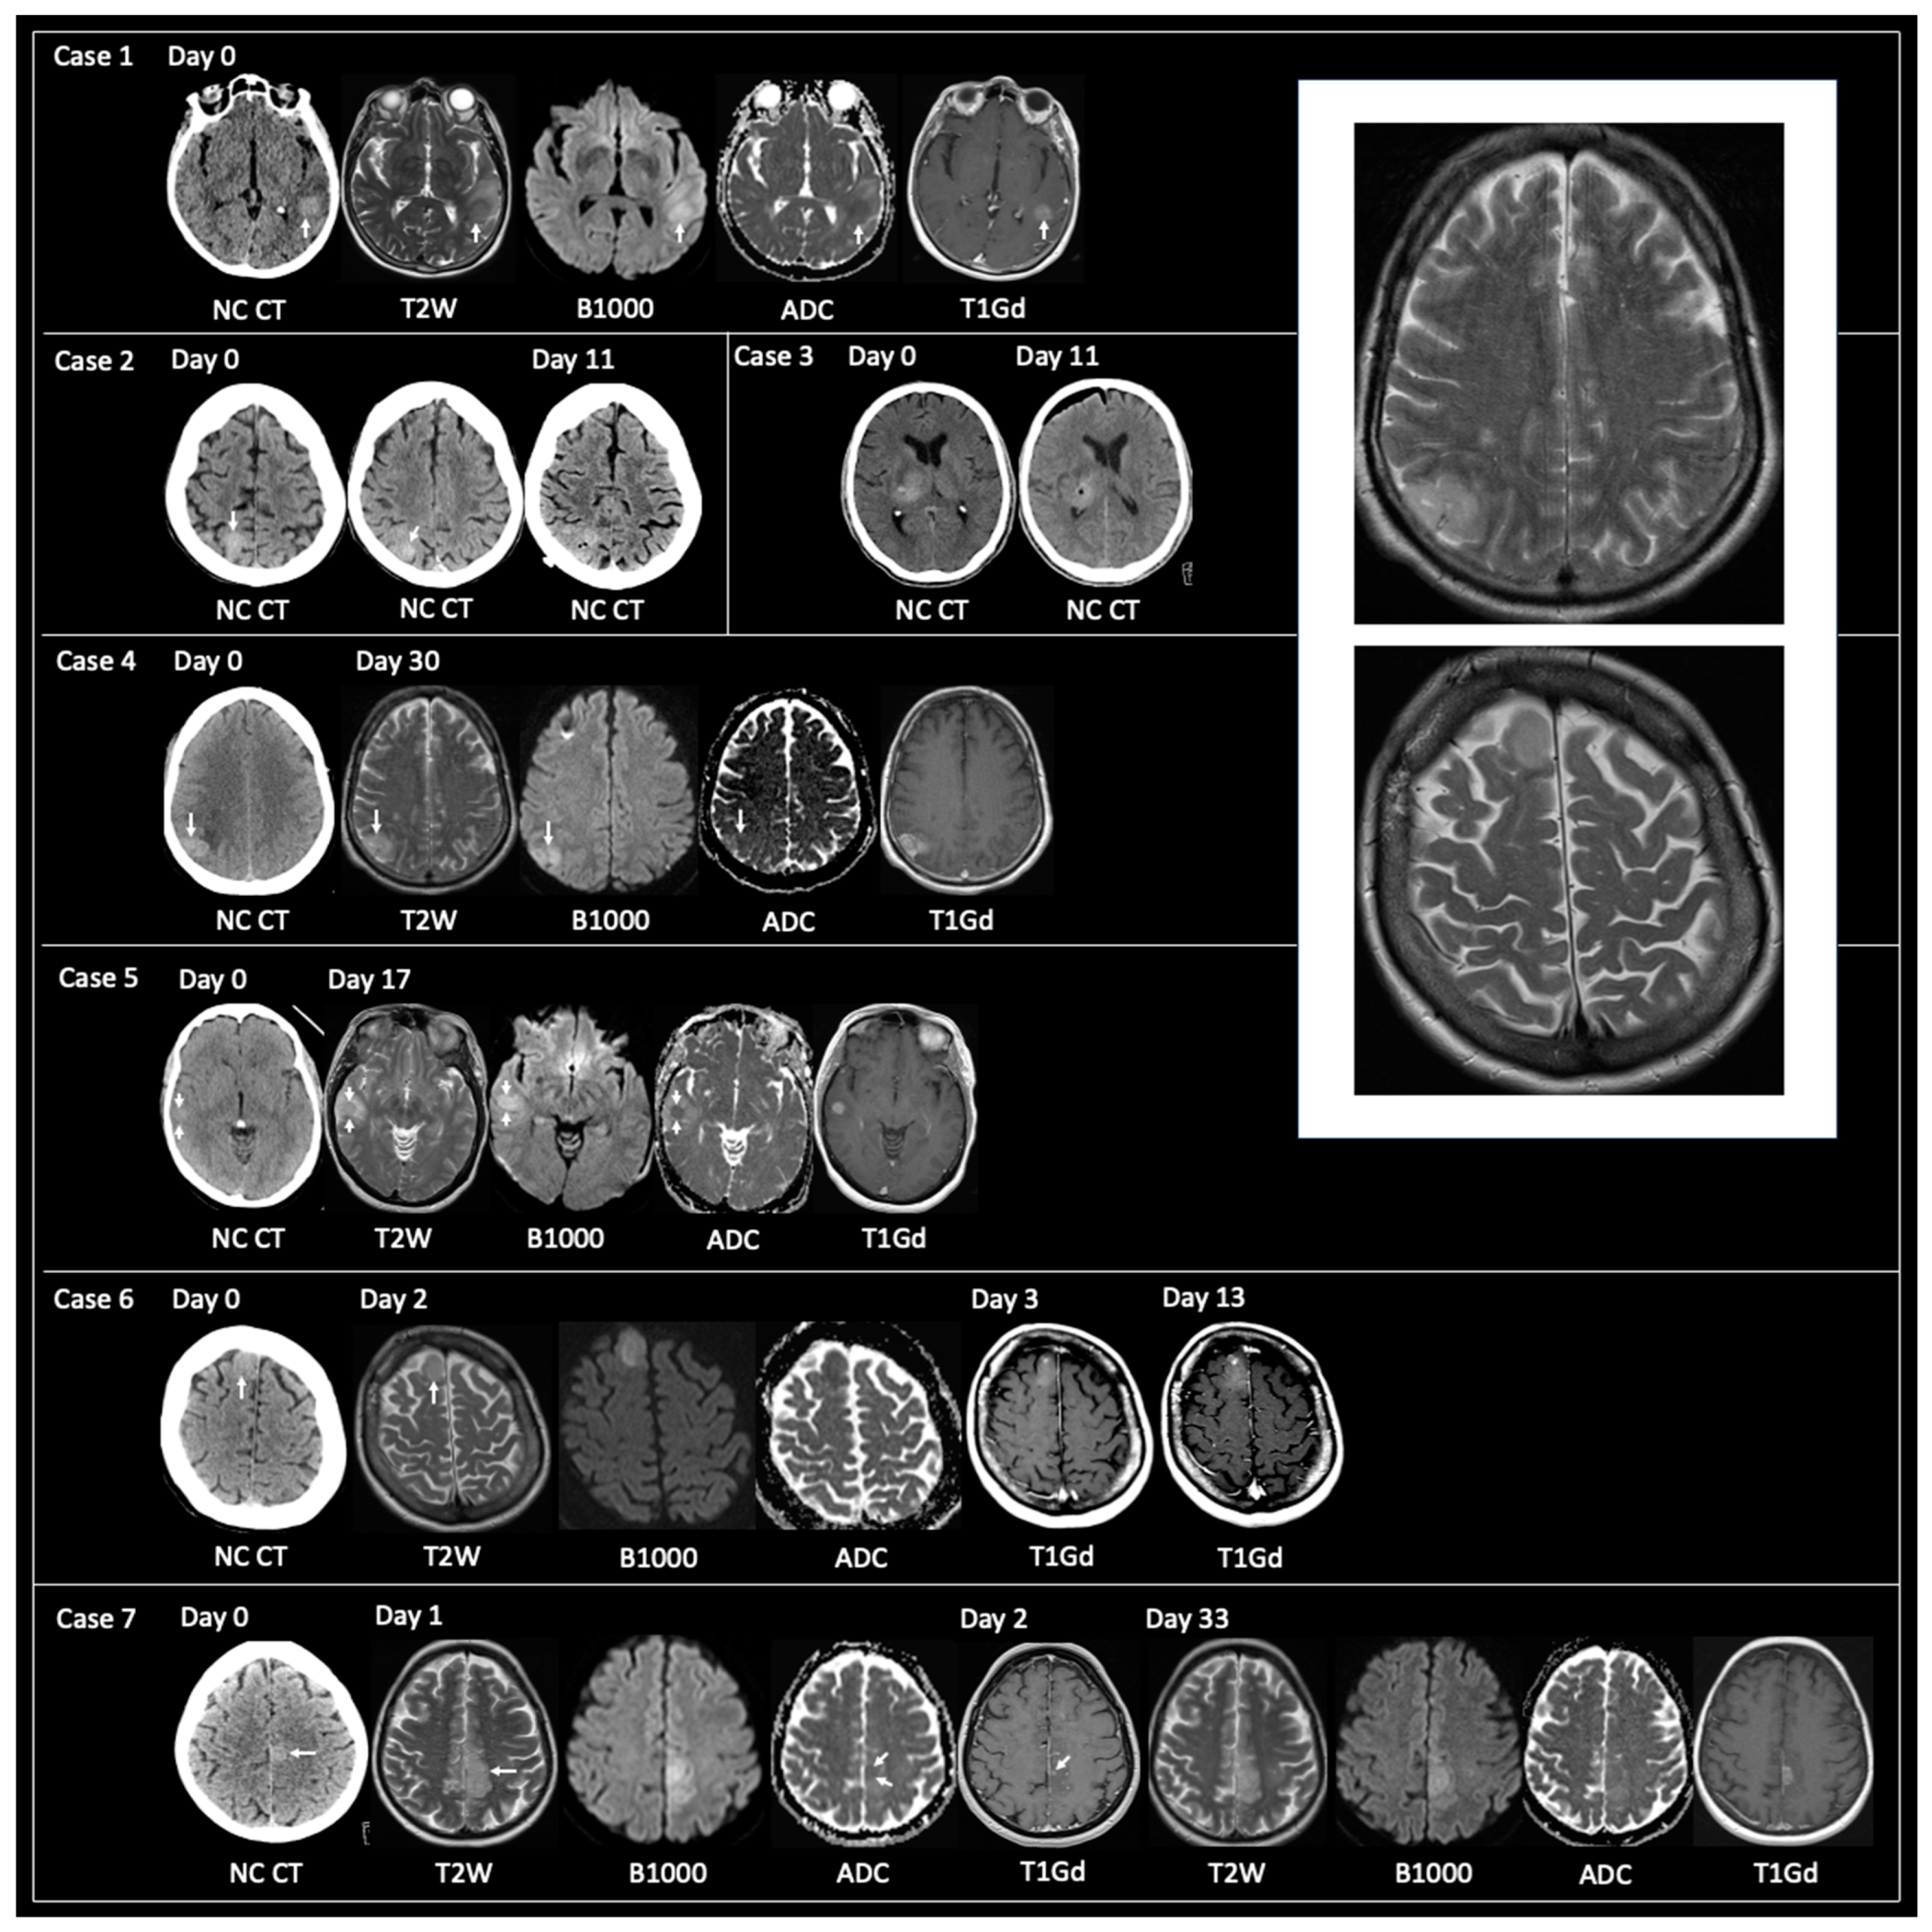

20 patients had a tissue diagnosis of GBM when imaging showed non-typical GBM. All patients had either a CT hyperdense or T2 iso-lesion: 3 of 20 patients had CT only, 7 of 20 had MRI only, and 10 of 20 had an initial CT followed by MRI with a mean duration between the imaging studies of 10 days (range 0–30). All 10 patients with CT and MRI showed a CT hyperdense lesion that corresponded to T2 iso. All 17 patients that had MRI had T1Gd and the enhancement patterns of the 17 lesions were as follows: none = 1, solid = 6, and nodular = 10. Here, 16 of the 17 patients that had MRI had accompanying DWI, and all 16 lesions showed reduced diffusivity. Examples of lesions with non-typical GBM are shown in Figure 2—note case 7 that shows an intratumoral focus of CT hyperdensity that progresses at a faster rate than the rest of the tumor.

Figure 2.

Examples of the imaging of non-typical GBM at the time of tissue sampling. Case 1: 72-year-old female presented with sudden-onset dysphasia. Unenhanced (non-intravenous contrast administration) CT (NC CT) showed a hyperdense lesion in the posterior aspect of the left superior temporal gyrus (arrow). MRI obtained on the same day showed that the lesion had corresponding T2 iso, solid enhancement, and reduced diffusivity (high B1000, low apparent diffusion coefficient (ADC)). Case 2: 74-year-old female was referred for memory impairment. Unenhanced CT showed a hyperdense lesion in the right superior parietal lobule (two contiguous CT slices shown). No MRI was obtained due to the patient having an incompatible permanent pacemaker. Unenhanced CT at day 11 showed post-biopsy appearances with small volume pneumocephalus within the hyperdense lesion. Case 3: 62-year-old male presented with left-sided weakness. Unenhanced CT showed a hyperdense lesion in the right thalamus (left image). Post-biopsy unenhanced CT (right image) with frontal subdural pneumocephalus and small focus of pneumocephalus at the biopsy site. MRI was contraindicated. Case 4: 50-year-old male presented with a seizure. Unenhanced CT revealed a hyperdense lesion in the right inferior parietal lobule. MRI at day 30 showed corresponding T2 iso, reduced diffusivity, and solid enhancement. Case 5: 56-year-old female presented with a seizure. Unenhanced CT at day 0 showed a hyperdense lesion in the right temporal lobe. MRI on day 17 showed that the lesion was T2 iso, had internal reduced diffusivity with corresponding solid enhancement. Case 6: 52-year-old female presented with a seizure. Hyperdense lesion in the anterior aspect of the right superior frontal gyrus on unenhanced CT at day 0. This had corresponding T2 iso and reduced diffusivity on MRI obtained on day 2. T1-weighted post-gadolinium (T1Gd) imaging obtained on day 3 and day 13 showed solid tumoral enhancement increasing in size over the 10-day interval. Case 7: 56-year-old male presented with a seizure. Unenhanced CT demonstrated a hyperdense lesion in the left paracentral lobule with surrounding low attenuation in left frontal and parietal lobes. MRI on day 1 revealed a T2 iso infiltrative lesion with a focus of reduced diffusivity and tiny dot of solid enhancement in the area of hyperdensity shown on the initial CT. MRI at day 33 showed a solid tumor (no necrosis) with a greater volume of solid enhancement at the site of prior CT hyperdensity. The Box in the top right of the image shows two enlarged examples of GBM where the tumor signal on T2-weighted imaging is isointense (T2 iso) to grey matter (taken from Cases 4 and 6). NC CT—non-contrast CT, T2W—T2-weighted, B1000—DWI, ADC—apparent diffusion coefficient map of DWI, T1Gd—T1-weighted post-gadolinium.